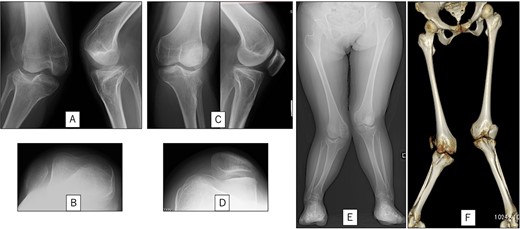

A 23-year-old woman presented with bilateral knee pain and gait abnormalities owing to marked lower extremity deformity. She was diagnosed with EVC as a child but had never been followed up by orthopedics because she was not in pain. On physical examination, marked valgus instability was observed in both knees, and the motion of both knees ranged from 10° to 135°. Radiographic examinations of both knees, including computed tomography, showed valgus deformity, lateral and anterior depression of the proximal lateral tibial plateau, and external rotation deformity of the lower leg. Patellar dislocation was observed in the right knee (Fig. 1). The radiological angles are presented in Table 1. The right knee underwent surgery first, followed by the left 10 months later. Lateral and medial skin incisions were made. Extensive lateral retinacular release, fractional lengthening of the distal lateral hamstring, and Z-lengthening of the iliotibial band were then performed. At this stage, peroneal nerve strain was identified, and decompression of the peroneal nerve was performed. Osteotomy was subsequently performed on the tibia. Closed-wedge varus and derotational osteotomy of the proximal tibia and open-wedge varus osteotomy of the distal femoral varus were performed. In addition, vastus medialis advancement was performed on the right knee, and patellar realignment was achieved in extension (Fig. 2). However, the knee showed a subluxation tendency owing to flexion of >30°; therefore, the postoperative rehabilitation plan progressed more slowly than that of the left knee. Range of motion training began on the left knee immediately after surgery without any restrictions, but on the right knee only after 3 weeks of postoperative immobilization in the extended position. However, ambulation exercise was performed on both knees with no loading for 3 weeks, then partial loading was initiated, and full loading was permitted at 8 weeks postoperatively. Early postoperative standing radiography showed residual mild valgus deformity of the lower limbs (Fig. 2, Table 2). In addition, the right knee showed patellar re-dislocation 2 months postoperatively, and the patellar deformity gradually progressed owing to the femoral implant; therefore, the patient underwent implant removal, tibial tubercle transfer, and medial patellofemoral ligament reconstruction 1.5 years after the initial surgery (Fig. 3). Six months later, she fell while walking and developed a fracture at the osteotomy of the right femur; open reduction and internal fixation were performed (Fig. 4). The remaining years passed uneventfully, and 10 years after the initial surgery, the patient still had mild valgus deformity of the lower limbs, but had no recurrence other than that experienced immediately after surgery, no complaints of knee pain, and a stable gait (Fig. 5, Table 2).

Preoperative radiography and computed tomography: (A) anteroposterior and lateral views of the right knee, (B) skyline view of the right knee, (C) anteroposterior and lateral views of the left knee, (D) skyline view of the left knee, (E) standing anteroposterior view, and (F) 3D image of the entire lower limb.